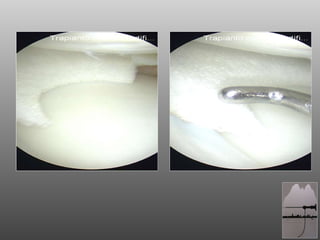

RAGAZZO DI 18aa, ATTIVO (CALCIO DILETTANTI) A 16aa SUTURA MENISCALE CORPO MENISCO ESTERNO OUT-IN  A 17 BLOCCO ARTICOLARE POST-TRAUMA: ARTROSCOPIA

RAGAZZO DI 18aa,ATTIVO (CALCIO DILETTANTI) A 16aa SUTURA MENISCALE CORPO MENISCO ESTERNO OUT-IN A 17 BLOCCO ARTICOLARE POST-TRAUMA: ARTROSCOPIA